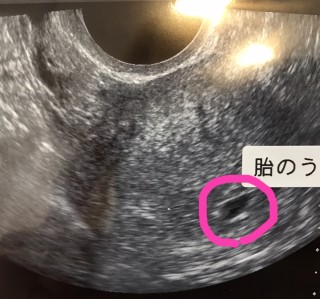

3日前には確認できなかった胎嚢が、無事に5w0dで確認できました!大きさは不明ですが、外枠のメモリから判断して、4-5㎜かと思われます。次の診察は9日後です。無事に胎芽・心拍を確認できますように…!